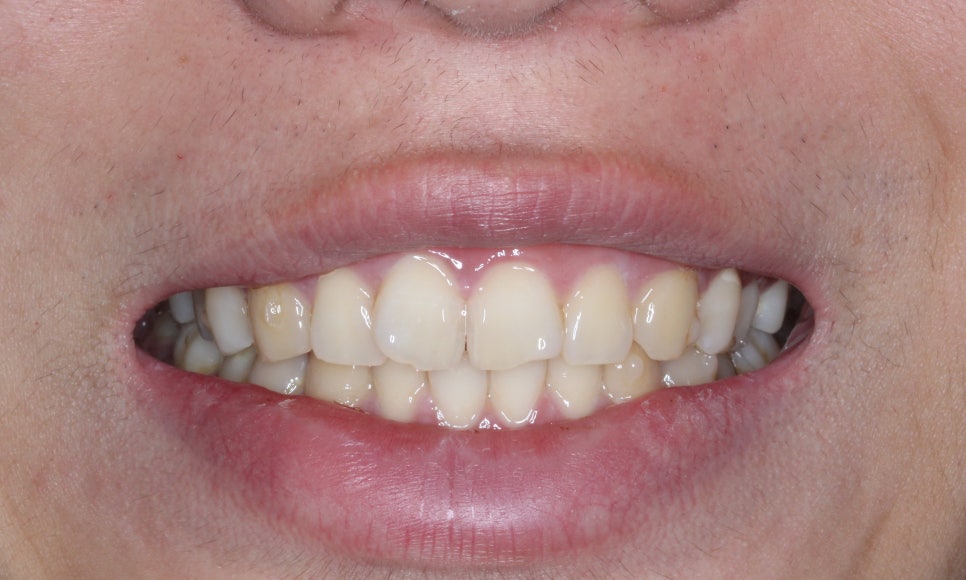

정면에서 보아도 확실히

교정 전과 달리 정돈된 모습이네요!

문제였던 11번, 12번 치아 역시

V자 형태가 아닌 부드러운 곡선을

띠게 되었습니다!